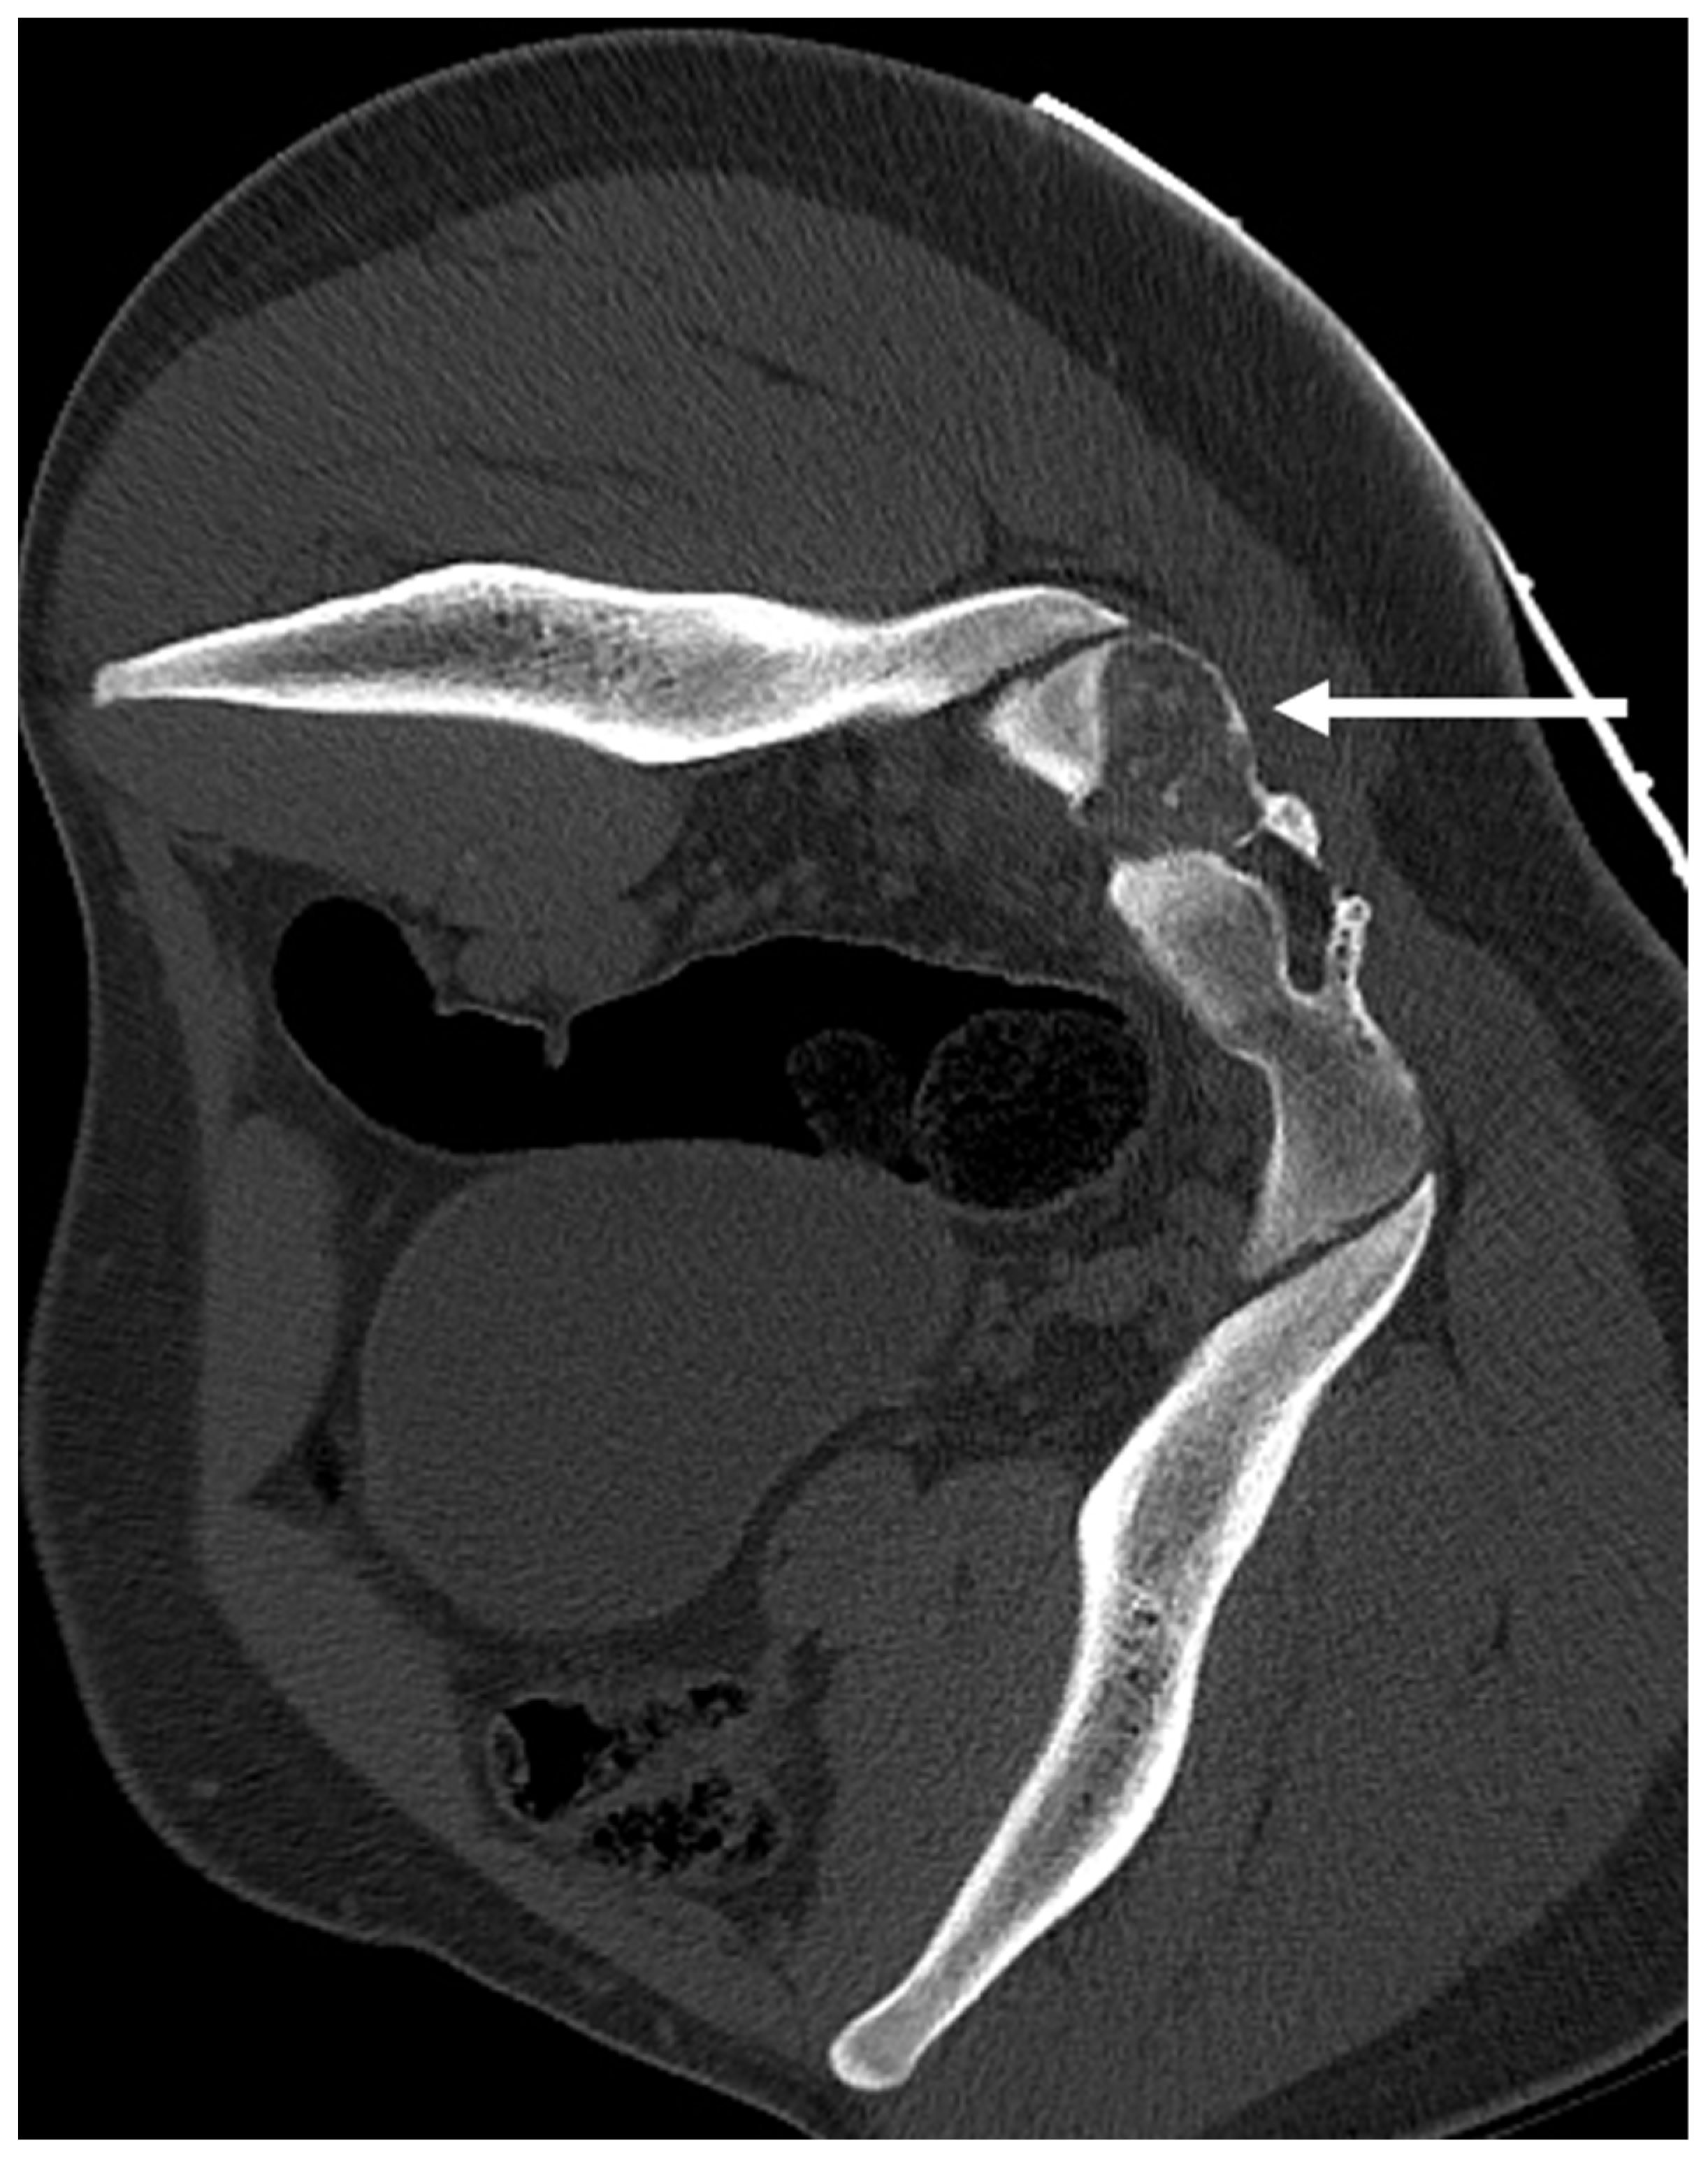

| Osteochondroma | Lesion continuity with cortex and medulla. | Cartilage cap |